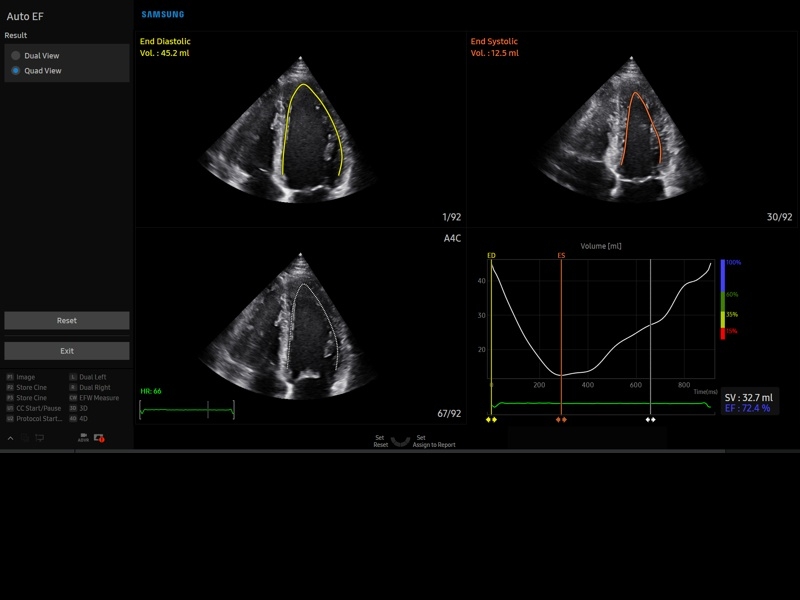

• Пакет кардиологических исследований.

М-режим:измерение диаметра аорты, передне-заднего размера ЛП, толщины МЖП (систолическая и диастолическая), толщины ЗСЛЖ (систолическая и диастолическая), размеров ЛЖ и ПЖ (систолический и диастолический), ФВ (Teichholz).

B-режим:измерение диаметра аорты (восходящей, дуги, нисходящей, на уровне синусов Вальсальвы, на уровне створок аортального клапана), определение размеров ЛП и ПП (максимальный, минимальный, систолический, диастолический, переднее-задний, верхнее-нижний, медиально-латеральный), расчет объемов ЛП и ПП, объемов ЛЖ (метод "Площадь-Длина", метод дисков (Simpson)), массы миокарда ЛЖ, индекса массы миокарда ЛЖ.